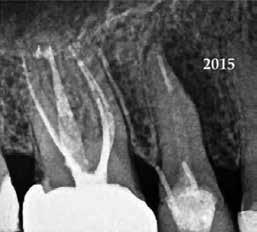

Krell és Caplan kutatásában 2086 repedt fogat vizsgáltak meg. A vizsgált fogak között leggyakrabban a második alsó nagyőrlőfogak (36%), majd ezt követően az első alsó nagyőrlők (27%), és végül az első felső nagyőrlők (18%) fordultak elő. A kutatási eredményeik szerint a fogbél állapota nem befolyásolta jelentős mértékben a kezelés várható kimenetelét. (Irreverzibilis pulpitis 85%; necrosis 80%; korábban gyökérkezelt 74%). A kimenetel szempontjából ugyanígy indifferens volt a páciensek neme, életkora, a kezelés időpontja, a fog pozíciója, a fog helyreállítása során használt anyag típusa, valamint az érintett fogfelszínek száma. 2014 júliusában egy 45 éves hölgy páciens azzal a panasszal kereste fel a rendelőnket, hogy nagyjából 10 napja egy fájdalmas duzzanat alakult ki a jobb felső első kisőrlője koronája mellett (14). A klinikai vizsgálat során egy amalgámtömést találtunk a panaszos fogban. A tömés széli zárása nem volt megfelelő, a disztális záróléc és a tömés között rést tapasztaltunk. A fog disztobukkális és linguális felszíne mellett 8 mm-es csontos tasakokat mértünk. A periapikális felvételen az 14-es foggyökér disztális felszínének megfelelően vertikális irányú radiolucens felritkulást észleltünk. A klinikai vizsgálat során a mesiális zárólécet kettéválasztó törésvonalat detektáltunk (17–18. ábra). A fogszenzibilitás vizsgálata során negatív eredményt kaptunk. A páciensnek ismertettük az elérhető terápiás lehetőségeket: 1, a 14-es fog eltávolítása, majd a foghiány 3 tagú cementezett híddal történő pótlása; 2, a 14-es fog eltávolítása, kemény- és lágyszöveti augmentáció, majd implantátum behelyezése; 3, a 14-es fog gyökérkezelése, gyökértömése és ezt követően a csücsökborítást biztosító restaurátum készítése. Arra is felhívtuk a páciens figyelmét, hogy a 3. terápiás lehetőség választása esetén nem tudjuk a fogmegtartás sikerességét garantálni, de végül – főként anyagi okok miatt – mégis ezt a terápiás opciót választotta. Fontos megjegyezni, hogy a repedt fogak ellátási lehetőségeit a törésvonal mélysége, elhelyezkedése, lefutása nagyban befolyásolja. A kezelés megtervezése során a fog és a fogat körülvevő szövetek állapotával kapcsolatos számtalan különböző faktort kell egyidejűleg figyelembe vennünk. A gyökérkezelést követően a gyökértömést meleg vertikális kondenzációs technikai alkalmazásával készítettük el (19. ábra). A hozzáférési nyílást folyékony és hibrid kompozit tömőanyag segítségével zártuk. A zárás elkészítése során a dr. David Clark által kifejlesztett Bioclear matricarendszert alkalmaztuk. A 6 éves kontroll során készített (2020) röntgenfelvételen a csontos defektus telődése volt megfigyelhető. Ez is a parodontális defektus gyógyulását igazolta (20–21. ábra).

17. ábra: A 14-es fog gyökerének disztális felszíne mellett vertikális csontpusztulásra utaló jelek észlelhetőek. Klinikailag ezen a területen 8 mm mélységű tasakmélységet mértünk. – 18. ábra: A 14-es fog disztális zárólécének megfelelően törésvonal észlelhető, ugyanakkor a csücskök teljes szeparálódására utaló jelek nem láthatóak. Az amalgámtömés eltávolítását követően jól megfigyelhető volt a törésvonal teljes lefutása. – 19. ábra: A gyökértömés elkészítése során meleg vertikális kondenzációs technikát alkalmaztunk. A felvételeken oldalcsatornák jelenlétére utaló jelek is észlelhetőek. – 20–21. ábra: A 2020-ban készült kontrollfelvételeken jól látható a csontos defektus telődése. A radiológiai jelek alapján (jól lekövethető gyökérhártyarés) a parodontális ligamentumok regenerációját is vélelmezzük.